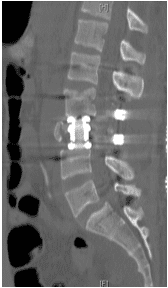

Surgery

Patient was operated and the spinal canal cleaned up of all bony fragments. The spine was fixed from the side and the back to take care of instability.

Patient was sent to a rehab facility after the surgery and she made a quick and complete recovery in 5-6 months.